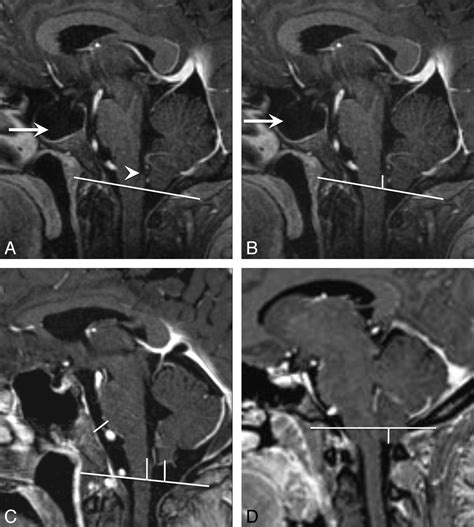

When these tonsils descend into the foramen magnum, the condition is often scrutinized by neurologists and neurosurgeons. The severity is generally measured by the number of millimeters that the tonsils extend below the line of the foramen magnum. While the medical community has debated what constitutes a "pathological" descent, a displacement of 5 millimeters or more is commonly used as a clinical threshold for a diagnosis of Chiari I malformation, though clinical symptoms are often a more important factor than the measurement alone.

If your doctor notes that your cerebral tonsils low lying appearance is clinically significant, they will likely move forward with a more comprehensive evaluation. An MRI of the brain and entire cervical spine is the gold standard for assessment. This allows the radiologist and neurologist to check for a syrinx—a fluid-filled cyst within the spinal cord—which can occur if the flow of spinal fluid is chronically blocked.

• Dynamic MRI: Sometimes, doctors will use special imaging techniques to observe the actual flow of cerebrospinal fluid around the foramen magnum while you are moving or during specific breathing maneuvers.